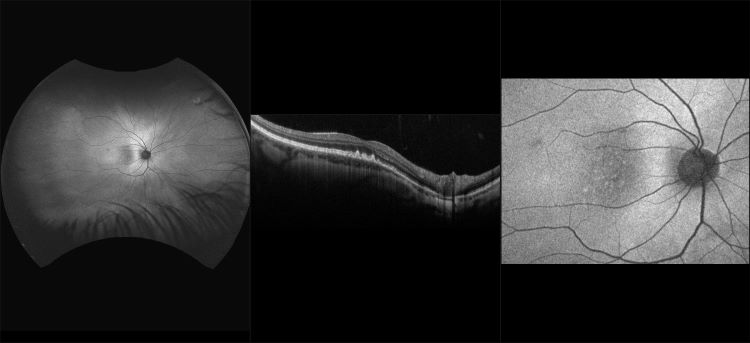

AMD Ryzen 5 1600 AF Review A Wildcard Server Option ServeTheHome deals, Amazon AMD Ryzen 5 1600 65W AM4 Processor with Wraith Stealth deals, AMD Ryzen 5 1600 AF Review TechSpot deals, AMD Ryzen 5 1600 AF Review TechSpot deals, AMD Ryzen 5 1600 AF Review A Wildcard Server Option Page 3 of 3 deals, AMD Ryzen 5 1600 AF 3.2GHz 6 Core Socket AM4 CPU deals, AMD Ryzen 5 1600 AF Review TechSpot deals, The US 85 AMD Ryzen 5 1600 AF looks to be a new 12nm Zen part and deals, AMD Ryzen 5 1600 AF 3.2GHz 6 Core Socket AM4 CPU deals, AMD s Ryzen 3 1200 AF the Original Ryzen 3 1200 CPUs Compared deals, Amazon AMD Ryzen 5 1600 65W AM4 Processor with Wraith Stealth deals, AMD Ryzen 5 1600 AF Review TechSpot deals, AMD s alleged Ryzen 5 3600 AF may give same performance as Ryzen deals, AMD Ryzen 5 1600 65W AM4 Processor with Wraith Amazon deals, AMD Ryzen 5 1600 AF review 12nm Zen refresh of 1600 for 85USD deals, RYZEN 5 1600AF CPU AMD RYZEN 5 1600 AF Online Computer Store deals, Ryzen 1600 deals, AMD Ryzen 5 2600X 1600 AF 2024 Revisit vs. 5800X3D 7800X3D deals, AMD Ryzen 5 1600 AF 3.2GHz 6 Core Socket AM4 CPU deals, Age related Macular Degeneration Case Study deals, AF image of geographic atrophy due to advanced AMD. In the area of deals, AMD Ryzen 5 1600 AF Review The Ultimate Value CPU deals, PC Upgrade Kit AMD Ryzen 5 1600 AF MSI A320M A PRO MAX Upgrade deals, Ryzen AF 2.0 Spotted Zen 3 Powered R5 3600 Shows on Romanian deals, California Atrophic AMD with Geographic Atrophy RG AF FA ICG deals, AMD Ryzen 5 1600 AF PC Upgrade Kit Gigabyte B450M DS3H V2 deals, AMD Ryzen 5 1600 AF 6 Core 3.20GHz 16MB L3 Cache Socket AM4 Processor deals, Buy AMD Ryzen 3 1200 AF 3.1GHz Quad Core Processor deals, AMD Ryzen 5 1600 YD1600BBM6IAF YD1600BBAFBOX deals, AMD Ryzen 5 1600 AF NAMD Benchmark ServeTheHome deals, AMD Ryzen 5 1600 AF AM4 12nm eBay deals, New AMD Ryzen 5 1600 AF CPU Review Benchmarks vs. Original R5 2600 3600 deals, AMD s New Ryzen 5 1600 AF Processor Is Cheap AF deals, AMD Ryzen 5 1600 AF Review TechSpot deals, PC Upgrade Kit AMD Ryzen 5 1600 AF MSI B450 TOMAHAWK MAX II deals, I found a used Ryzen 5 1600af for 300zl 70 . Is it worth it for deals, Monaco Early AMD w Drusen RG AF OCT deals, File C.14 38 14 20 a Spanish AF AMD Mirage F.1M Ala. 14.jpg deals, Examples of SW AF and NIR AF images from 3 patients. A A more deals, NEC Desktop Computer AMD 1.60 GHz Small Form Factor TNETPC AF WH Renewed deals, New AMD Ryzen 3 1200 AF 75 CPU Review Benchmarks Overclocking deals, AMD Ryzen 5 1600 AF Review TechSpot deals, The STROKE AF and PER DIEM Trials Detection of Atrial deals, File 053 AMD Falcon 20 ECM of FEKS 717 Skv. Royal Norwegian AF.jpg deals, AMD s alleged Ryzen 5 3600 AF may give same performance as Ryzen deals, The US 85 AMD Ryzen 5 1600 AF looks to be a new 12nm Zen part and deals, AMD Ryzen 5 1600 AF Review The Ultimate Value CPU deals, Silverstone Wet AMD Sub Retinal Fluid Full Steer RG AF deals, GIGABYTE unveils AMD Ryzen Threadripper 3995X beast AF workstations deals, AMD Ryzen 5 1600 AF Review A Wildcard Server Option ServeTheHome deals.